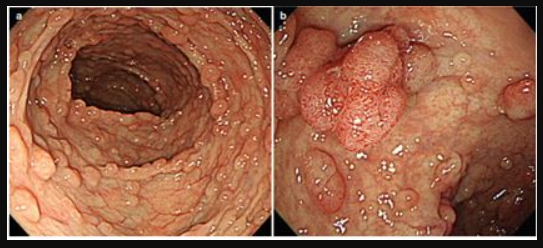

Hội chứng đa polyp gia đình và mối liên quan với ung thư đại trực tràng